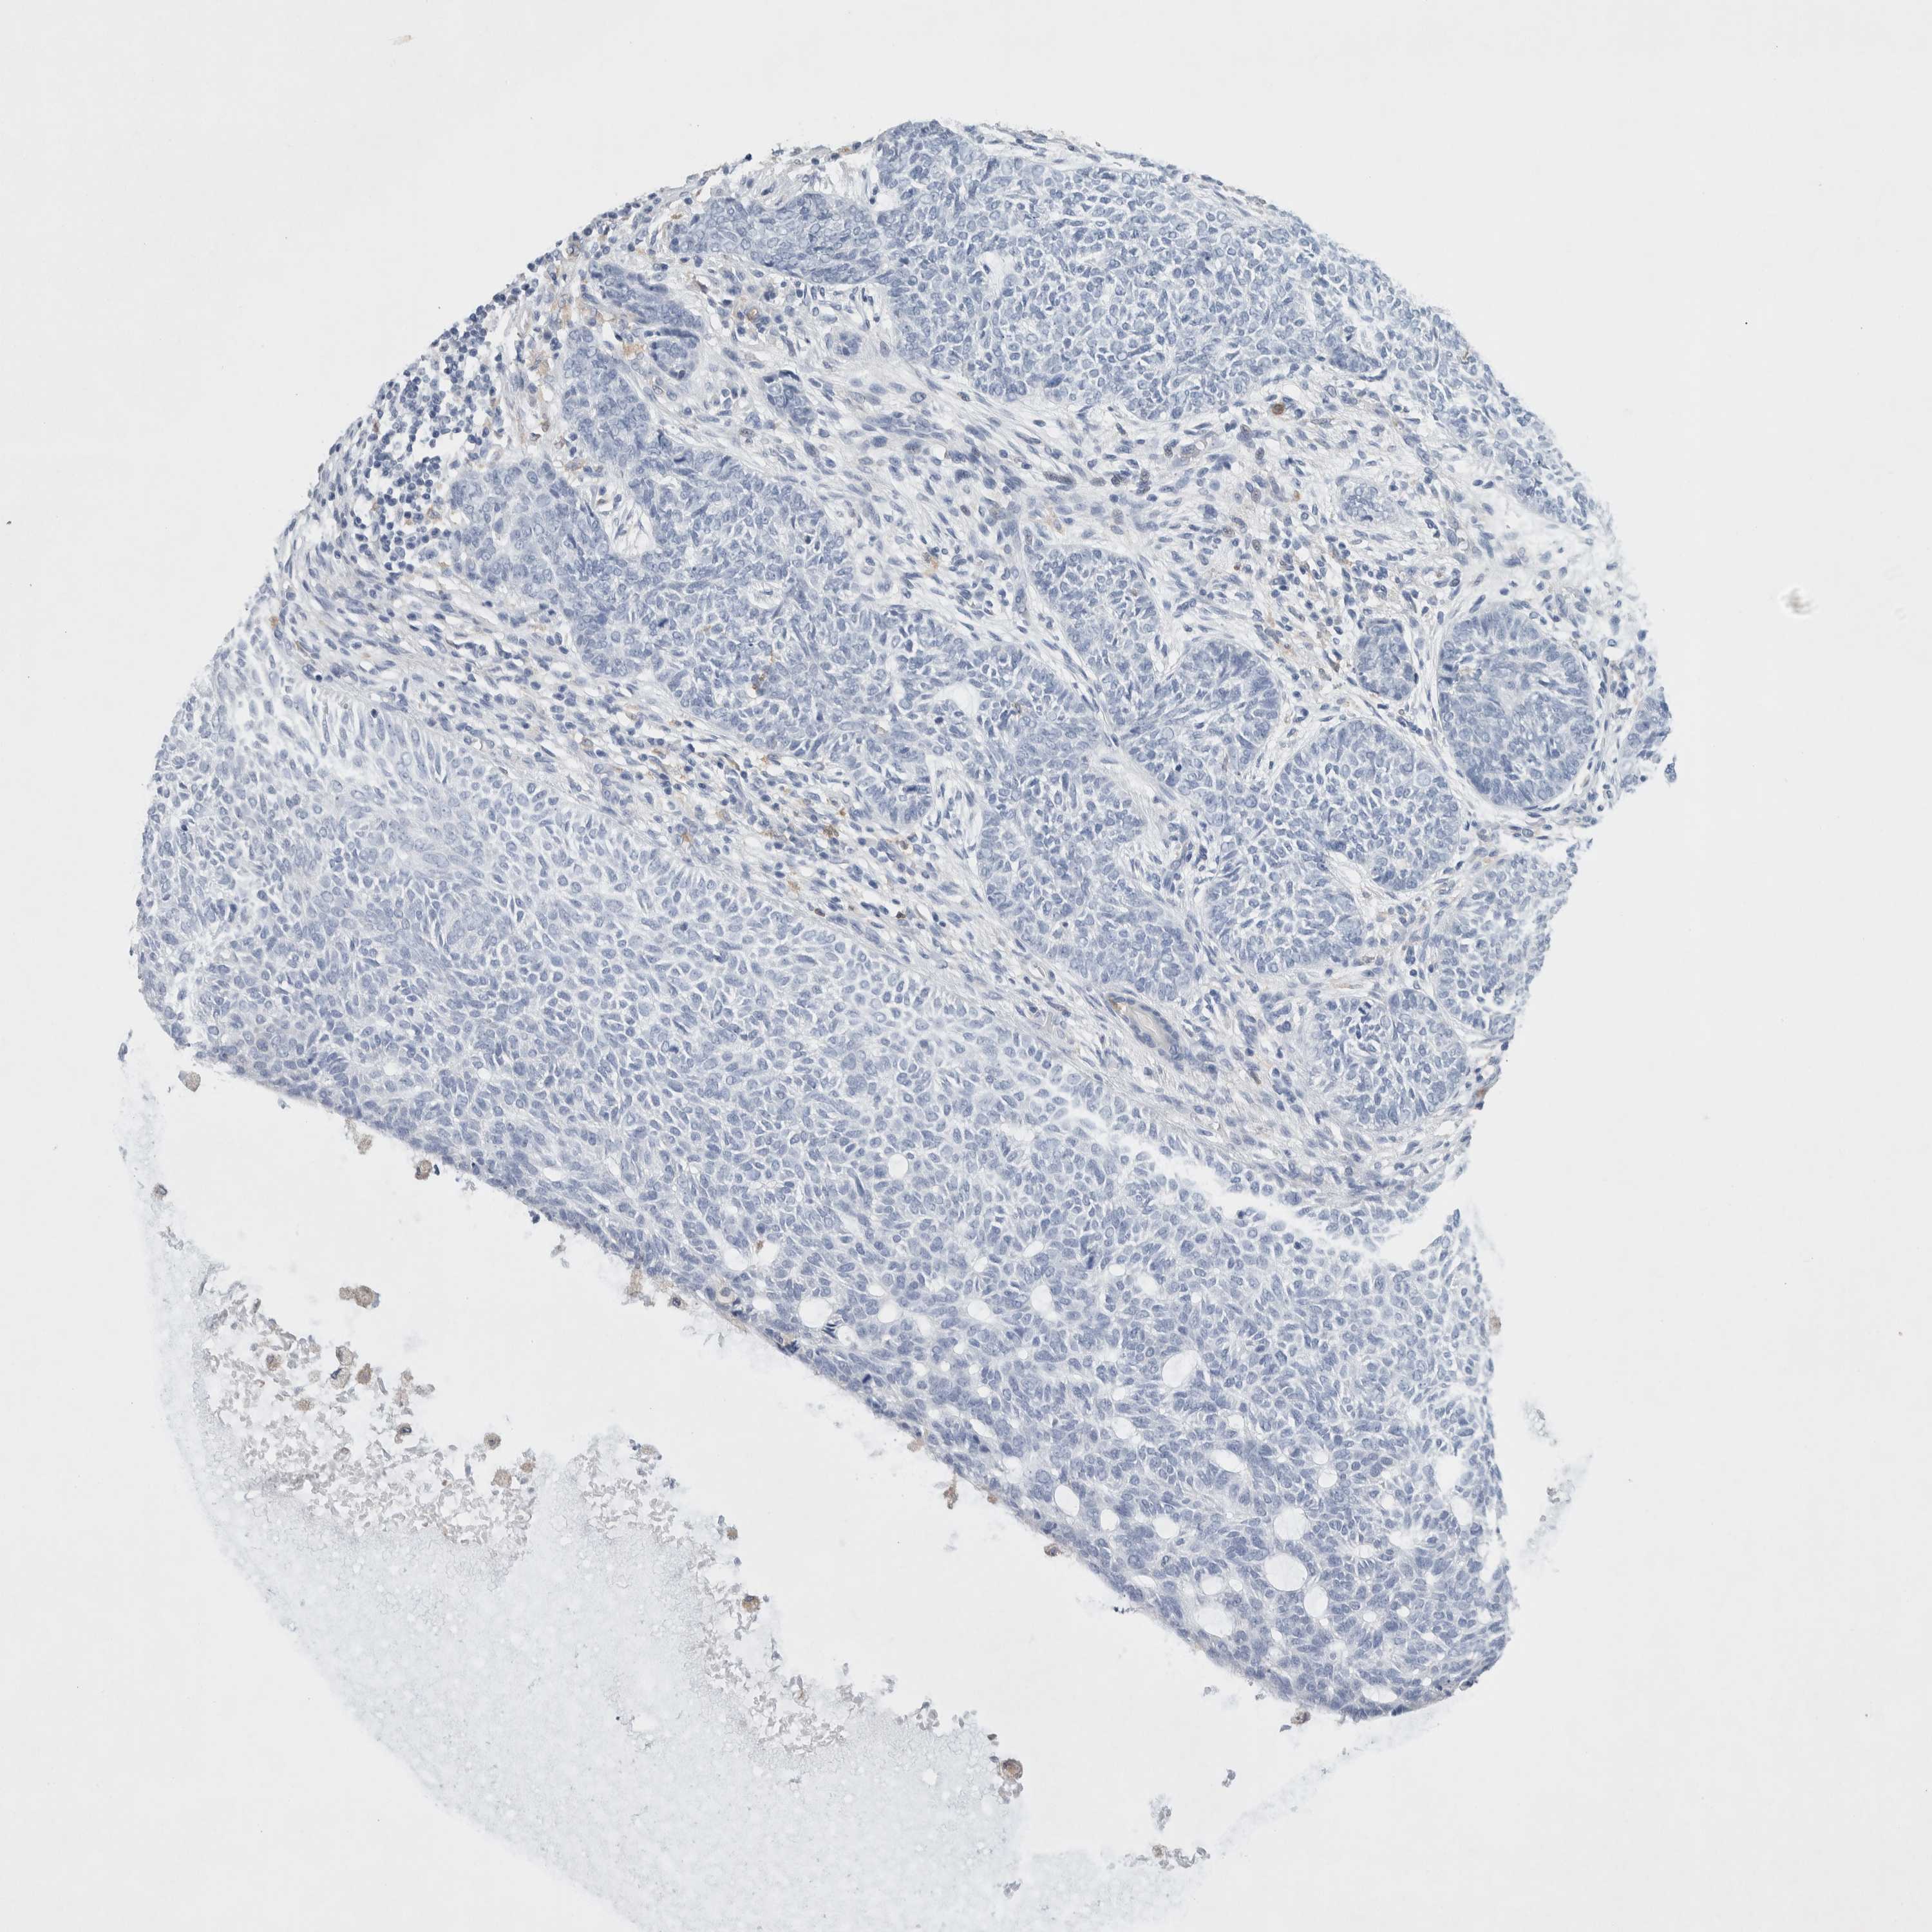

CANCER SKIN CANCER Show tissue menu

Basal cell and squamous cell cancer

SKIN CANCER - Protein expressioni

A mouse-over function shows sample information and annotation data. Click on an image to view it in a full screen mode. Samples can be filtered based on level of antibody staining by selecting one or several of the following categories: high, medium, low and not detected. The assay and annotation is described here.

Each image is clickable and will lead to virtual microscopy that enables deeper exploration of all samples and also displays staining intensity scores, fraction scores and subcellular localization as well as patient and tissue information for each sample.

Antibody HPA002327

Antibody HPA006040

Antibody CAB022160

Staining

Not detected

Negative

None

Squamous cell carcinoma, NOS

Basal cell carcinoma